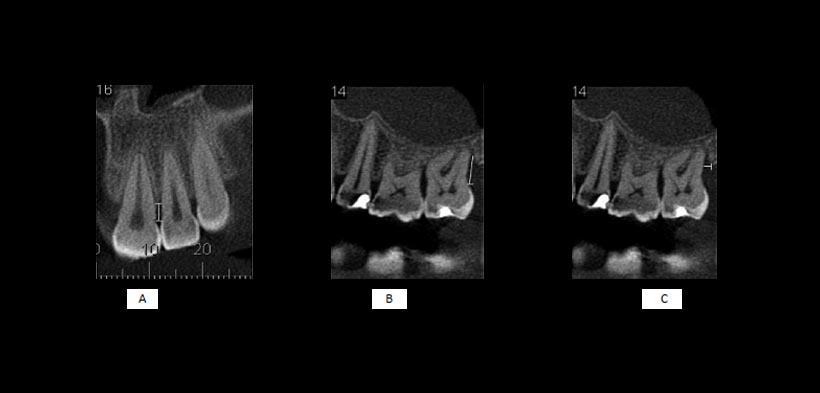

Un parámetro importante para la evaluación de la altura ósea es la distancia que existe entre la cresta del hueso alveolar a la unión del esmalte con el cemento (UCA). En la literatura existen amplias variaciones de la normalidad con respecto a ésta altura, que van desde 1 mm a 3 mm, aunque una distancia de 2 mm es más ampliamente aceptada como normal. En adultos jóvenes, la altura media del hueso en relación con la UCA es 1,4 mm y para las personas mayores de 45 años, este promedio se amplía a 3 mm (fig 1, 2, 3).

Fig 2. Imágenes de una tomografía cone beam que muestran las mediciones de las distancias: (A) de la unión cemento-esmalte (CEJ) a la cresta alveolar (AC) en la superficie mesial la pieza 2.2, (B) de la CEJ a la parte inferior del defecto y (C) la anchura del defecto en la superficie distal de la pieza 2.7 (líneas blancas).